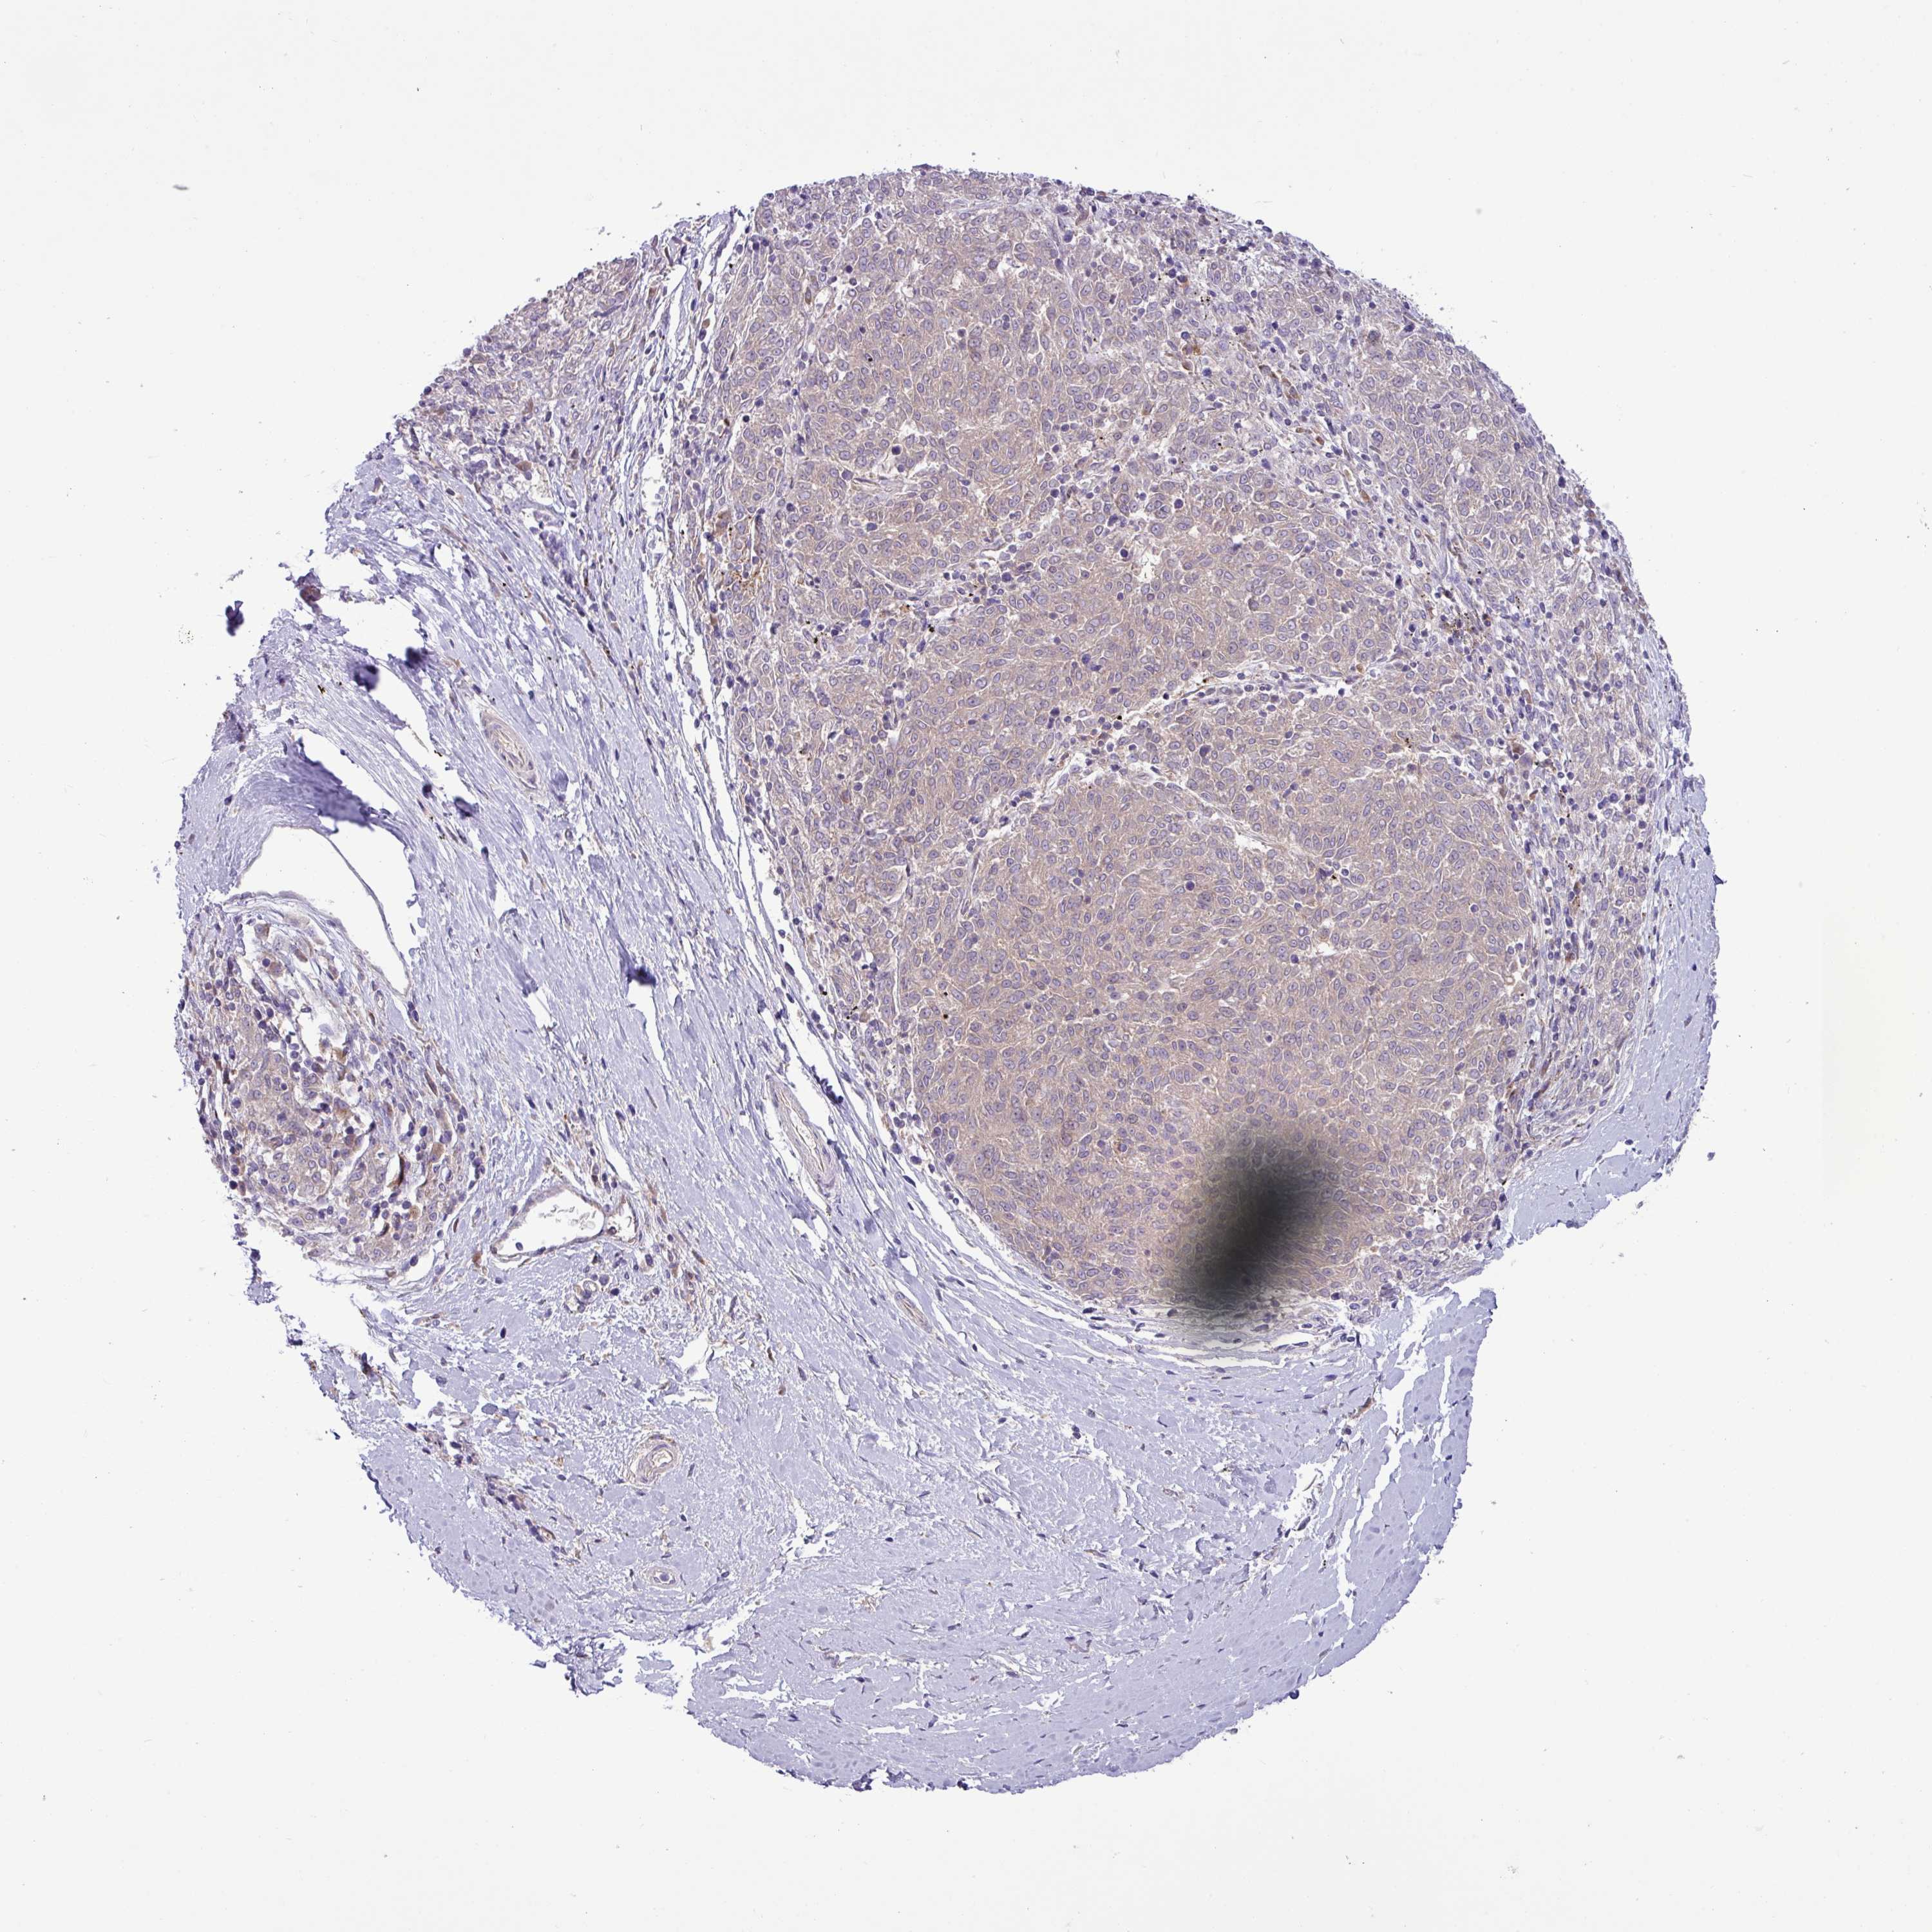

MELANOMA - Protein expressioni

A mouse-over function shows sample information and annotation data. Click on an image to view it in a full screen mode. Samples can be filtered based on level of antibody staining by selecting one or several of the following categories: high, medium, low and not detected. The assay and annotation is described here.

Note that samples used for immunohistochemistry by the Human Protein Atlas do not correspond to samples in the TCGA dataset.

Antibody stainingi

Antibody staining in the annotated cell types in the current human tissue is reported as not detected, low, medium, or high, based on conventional immunohistochemistry profiling in selected tissues. This score is based on the combination of the staining intensity and fraction of stained cells.

Each image is clickable and will lead to virtual microscopy that enables deeper exploration of all samples and also displays staining intensity scores, fraction scores and subcellular localization as well as patient and tissue information for each sample.

Antibody HPA051077

Staining

High

Medium

Low

Not detected

Intensity

Strong

Moderate

Weak

Negative

Quantity

>75%

75%-25%

<25%

None

Location

Nuclear

Cytoplasmic/membranous

Cytoplasmic/membranous,nuclear

Malignant melanoma, NOS

Malignant melanoma, Metastatic site